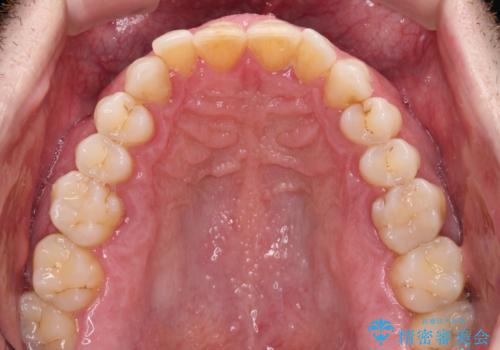

- 前歯でものを噛みきりたいとのことで来院された患者様です。

以前矯正治療を経験されたそうですが、舌の突出癖により上下前歯に隙間ができている様子でした。

舌の突出癖が改善されない限り、非接触改善は見込めないため、トレーニングを徹底するように指示しました。

舌のトレーニング自体は簡単なものですが、無意識下でも舌が突出しないようにしなければならないため、毎日継続することが最大の難関です。

時間はかかりましたがトレーニングを頑張ってくださり、無事に前歯を接触させることができました。